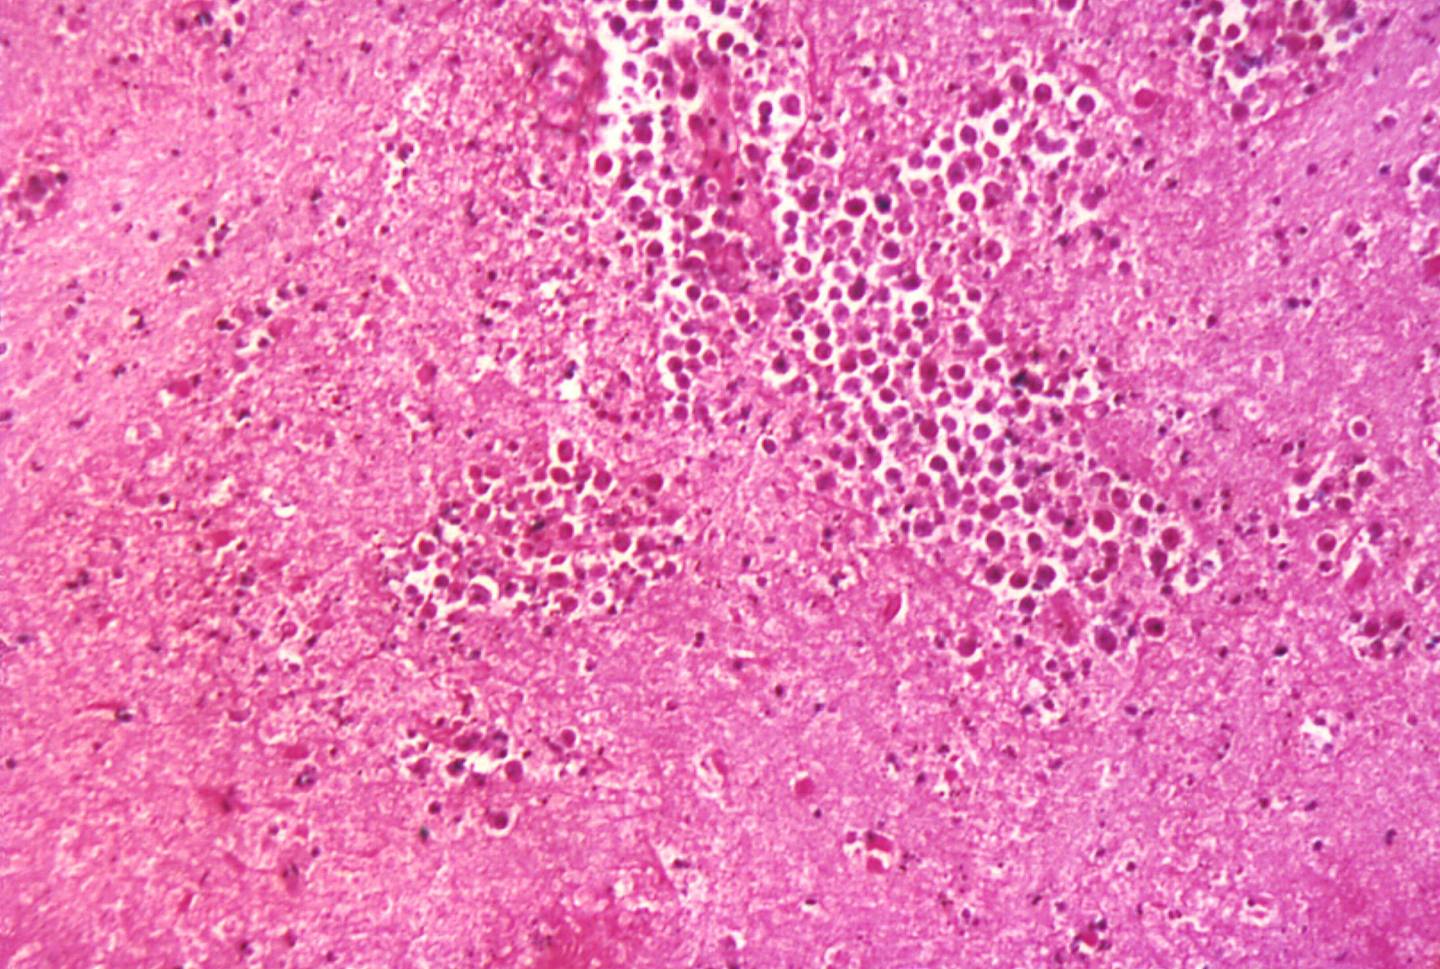

According to the CDC, Naegleria fowleri causes the onset of primary amebic meningoencephalitis (PAM), a brain infection that leads to the destruction of brain tissue and be fatal. Its symptoms mimic those of bacterial meningitis and include fever, headache, and nausea. Following the onset of symptoms, patients typically die from PAM within five days.